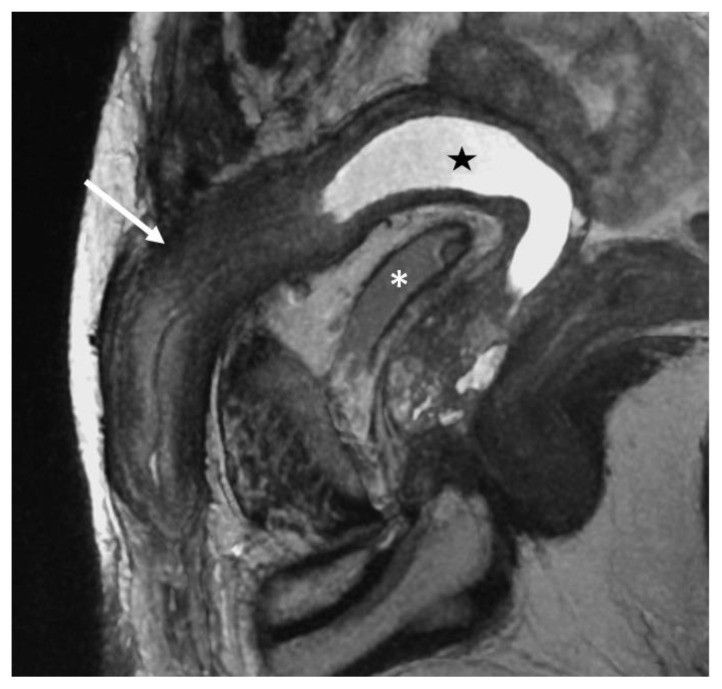

Contoh hasil pemeriksaan radiologi pada pengidap PMDS (europepmc.org)

Pria yang mengidap PMDS umumnya memiliki alat reproduksi laki-laki normal, dan alat kelamin normal pula. Namun tidak hanya itu, mereka juga dapat memiliki rahim dan saluran tuba yang dimiliki wanita.